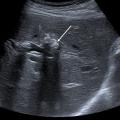

Échographie hépatique : examen clé du diagnostic

L’échographie hépatique est l’examen clé pour le diagnostic de syndrome LPAC. Celle-ci met typiquement en évidence les signes d’une microlithiase intrahépatique sous la forme d’images en « queue de comète » (échos de répétition liés à la vibration des microcristaux sous le faisceau d’ultrasons), de micro-­spots ou de « boue biliaire » (sludge) le long des canaux intrahépatiques (fig. 1A). Ces signes sont parfois difficilement identifiables, notamment en situation non sensibilisée et pour un opérateur non entraîné. Le principal diagnostic différentiel est représenté par les microhamartomes (ou complexes de von Meyenburg) qui peuvent parfois se présenter sous la forme d’artéfacts en queue de comète.9 Une échographie normale standard n’élimine pas le diag­nostic et il peut être nécessaire de répéter l’examen par un radiologue expérimenté et formé à la sémio­logie du syndrome LPAC. Moins fréquemment (5 à 10 % des cas), le syndrome LPAC peut se présenter sous la forme de vrais calculs (macrolithiases) intra- ou extrahépatiques (fig. 1B).4 Une lithiase vésiculaire n’est observée que chez un tiers des patients atteints de syndrome LPAC.

La cholangiographie par IRM est typiquement normale dans les formes habituelles, microlithiasiques, du syndrome LPAC. Elle n’est donc pas nécessaire au diagnostic dans la très grande majorité des situations. Elle doit être réalisée en cas de calculs intrahépatiques ou de dilatation des canaux biliaires en échographie afin d’évaluer le retentissement de ces calculs sur les voies biliaires et le parenchyme hépatique. Les calculs biliaires ne sont pas toujours visibles à l’imagerie par résonance magnétique (IRM), notamment quand leur taille est inférieure à 5 mm. Lorsqu’ils sont visibles, ils sont le plus souvent visualisés en hyposignal T1 et T2 sous forme de lacunes endobiliaires (fig. 2 A et 2B). Dans une série récente portant sur 125 patients suivis dans un centre expert et ayant tous eu une bili-IRM, 49 % présentaient des anomalies des canaux biliaires, parmi lesquelles 93 % de calculs intra­hépatiques et 38 % de dilatation des canaux biliaires.10 Ces anomalies morphologiques étaient plus fréquemment observées chez les porteurs d’un variant pathogène du gène ABCB4.